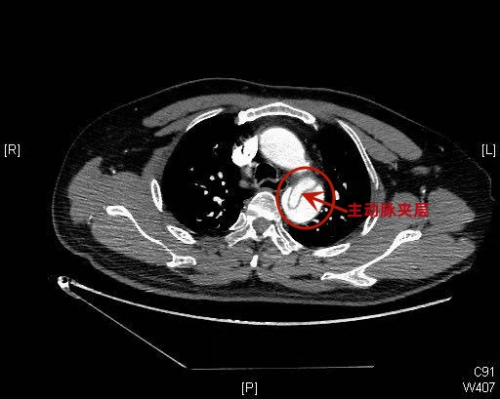

(南华大学附属长沙中心医院)急诊科。经相关检查后被诊断为主动脉夹层Stanford   B型,是一种严重的心血管急危重症。据家属介绍,患者发病前正在给小学四年级的女儿辅导作业,患者因孩子做作业拖拉而情绪激动,随后就突然感觉胸腹部刀割样剧烈疼痛,有濒死感,倒在了沙发上,家人发现后立即拨打120急救电话,送入医院。

(南华大学附属长沙中心医院)急诊科接诊医生、副主任医师赫留党介绍,患者蒋耀龙(化名)入院时面色潮红,表情痛苦,已经出现嗜睡症状,血压达175/107mmHg(正常范围90/60-120/80mmHg),心率98次/分,呼吸54次/分。经检查,患者被诊断出主动脉夹层Stanford B型,累及腹腔干及左髂总动脉、左肾动脉,情况危急,迅速转入急诊ICU,并请外周血管介入科进行会诊。外周血管介入科主任、主任医师赵扬程会诊后,结合患者当前的身体状况建议先积极控制血压,待收缩压稳定至100-130mmHg,平均动脉压维持在60-70mmHg-+;心率稳定至60次/分左右后再行介入手术。

赵扬程主任介绍,主动脉夹层是一种严重的心血管急危重症,是由于主动脉腔内的血液从主动脉内膜撕裂处进入主动脉中膜,使中膜分离,形成夹层血肿,并逐渐延伸剥离主动脉的内膜和中膜,随时可能造成血肿破裂,被称为“不定时炸弹”。常见的临床表现为突发的剧烈的胸痛或腰背部疼痛,疼痛性质为撕裂样或刀割样,并伴有血压升高。动脉夹层的病因和危险因素有高血压、动脉粥样硬化等。据了解,该患者没有进行过系统体检,患有高血压而不自知,这次发病前由于辅导孩子作业情绪激动、出现血压突发性急剧升高而造成了主动脉夹层。如果治疗不及时,严重可造成相应脏器缺血坏死、功能衰竭甚至死亡。